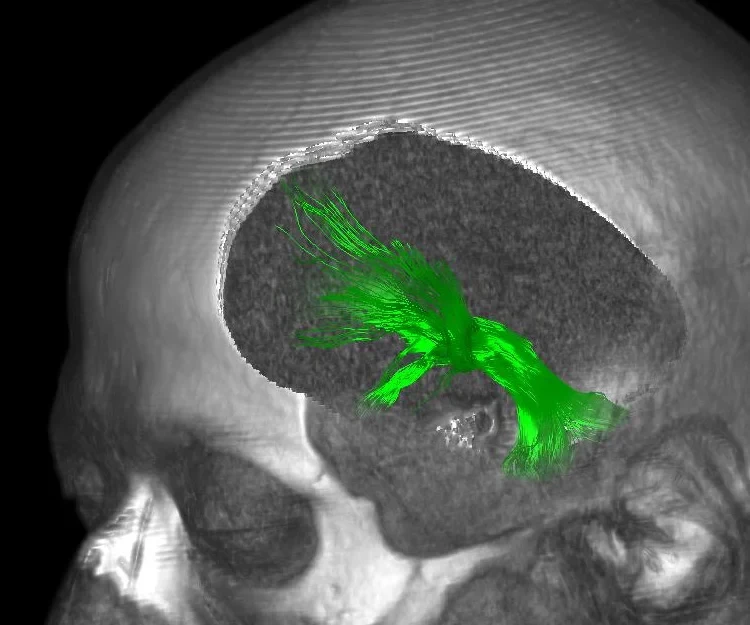

Hirnscan eines Patienten:

Hirnscan eines Patienten: - Das Mediale Vorderhirnbündel ist grün markiert. © Foto: Volker Arnd Coenen/Uni Freiburg

Beim Medialen Vorderhirnbündel handelt es sich um einen Nervenstrang, der sich vom tief liegenden Hirnstamm bis zur stirnseitigen Hirnrinde zieht. An einer bestimmten Stelle ist das Bündel besonders schmal, weil die einzelnen Nervenfasern hier eng beieinander liegen. „An diesem Ort erreichen wir mit wenig Strom ein Maximum an Wirkung“, erläutert Prof.  Coenen, der neuerdings die Abteilung Stereotaktische und Funktionelle Neurochirurgie am Universitätsklinikum Freiburg leitet. Das Mediale Vorderhirnbündel ist zentraler Teil eines Euphorie-Schaltkreises, der Teil des Belohnungssystems des Gehirns ist. Was die Stimulation in den Nervenzellen genau bewirkt, ist noch nicht bekannt. Aber offensichtlich verändert sie die Stoffwechselaktivität in verschiedenen Gehirnzentren.